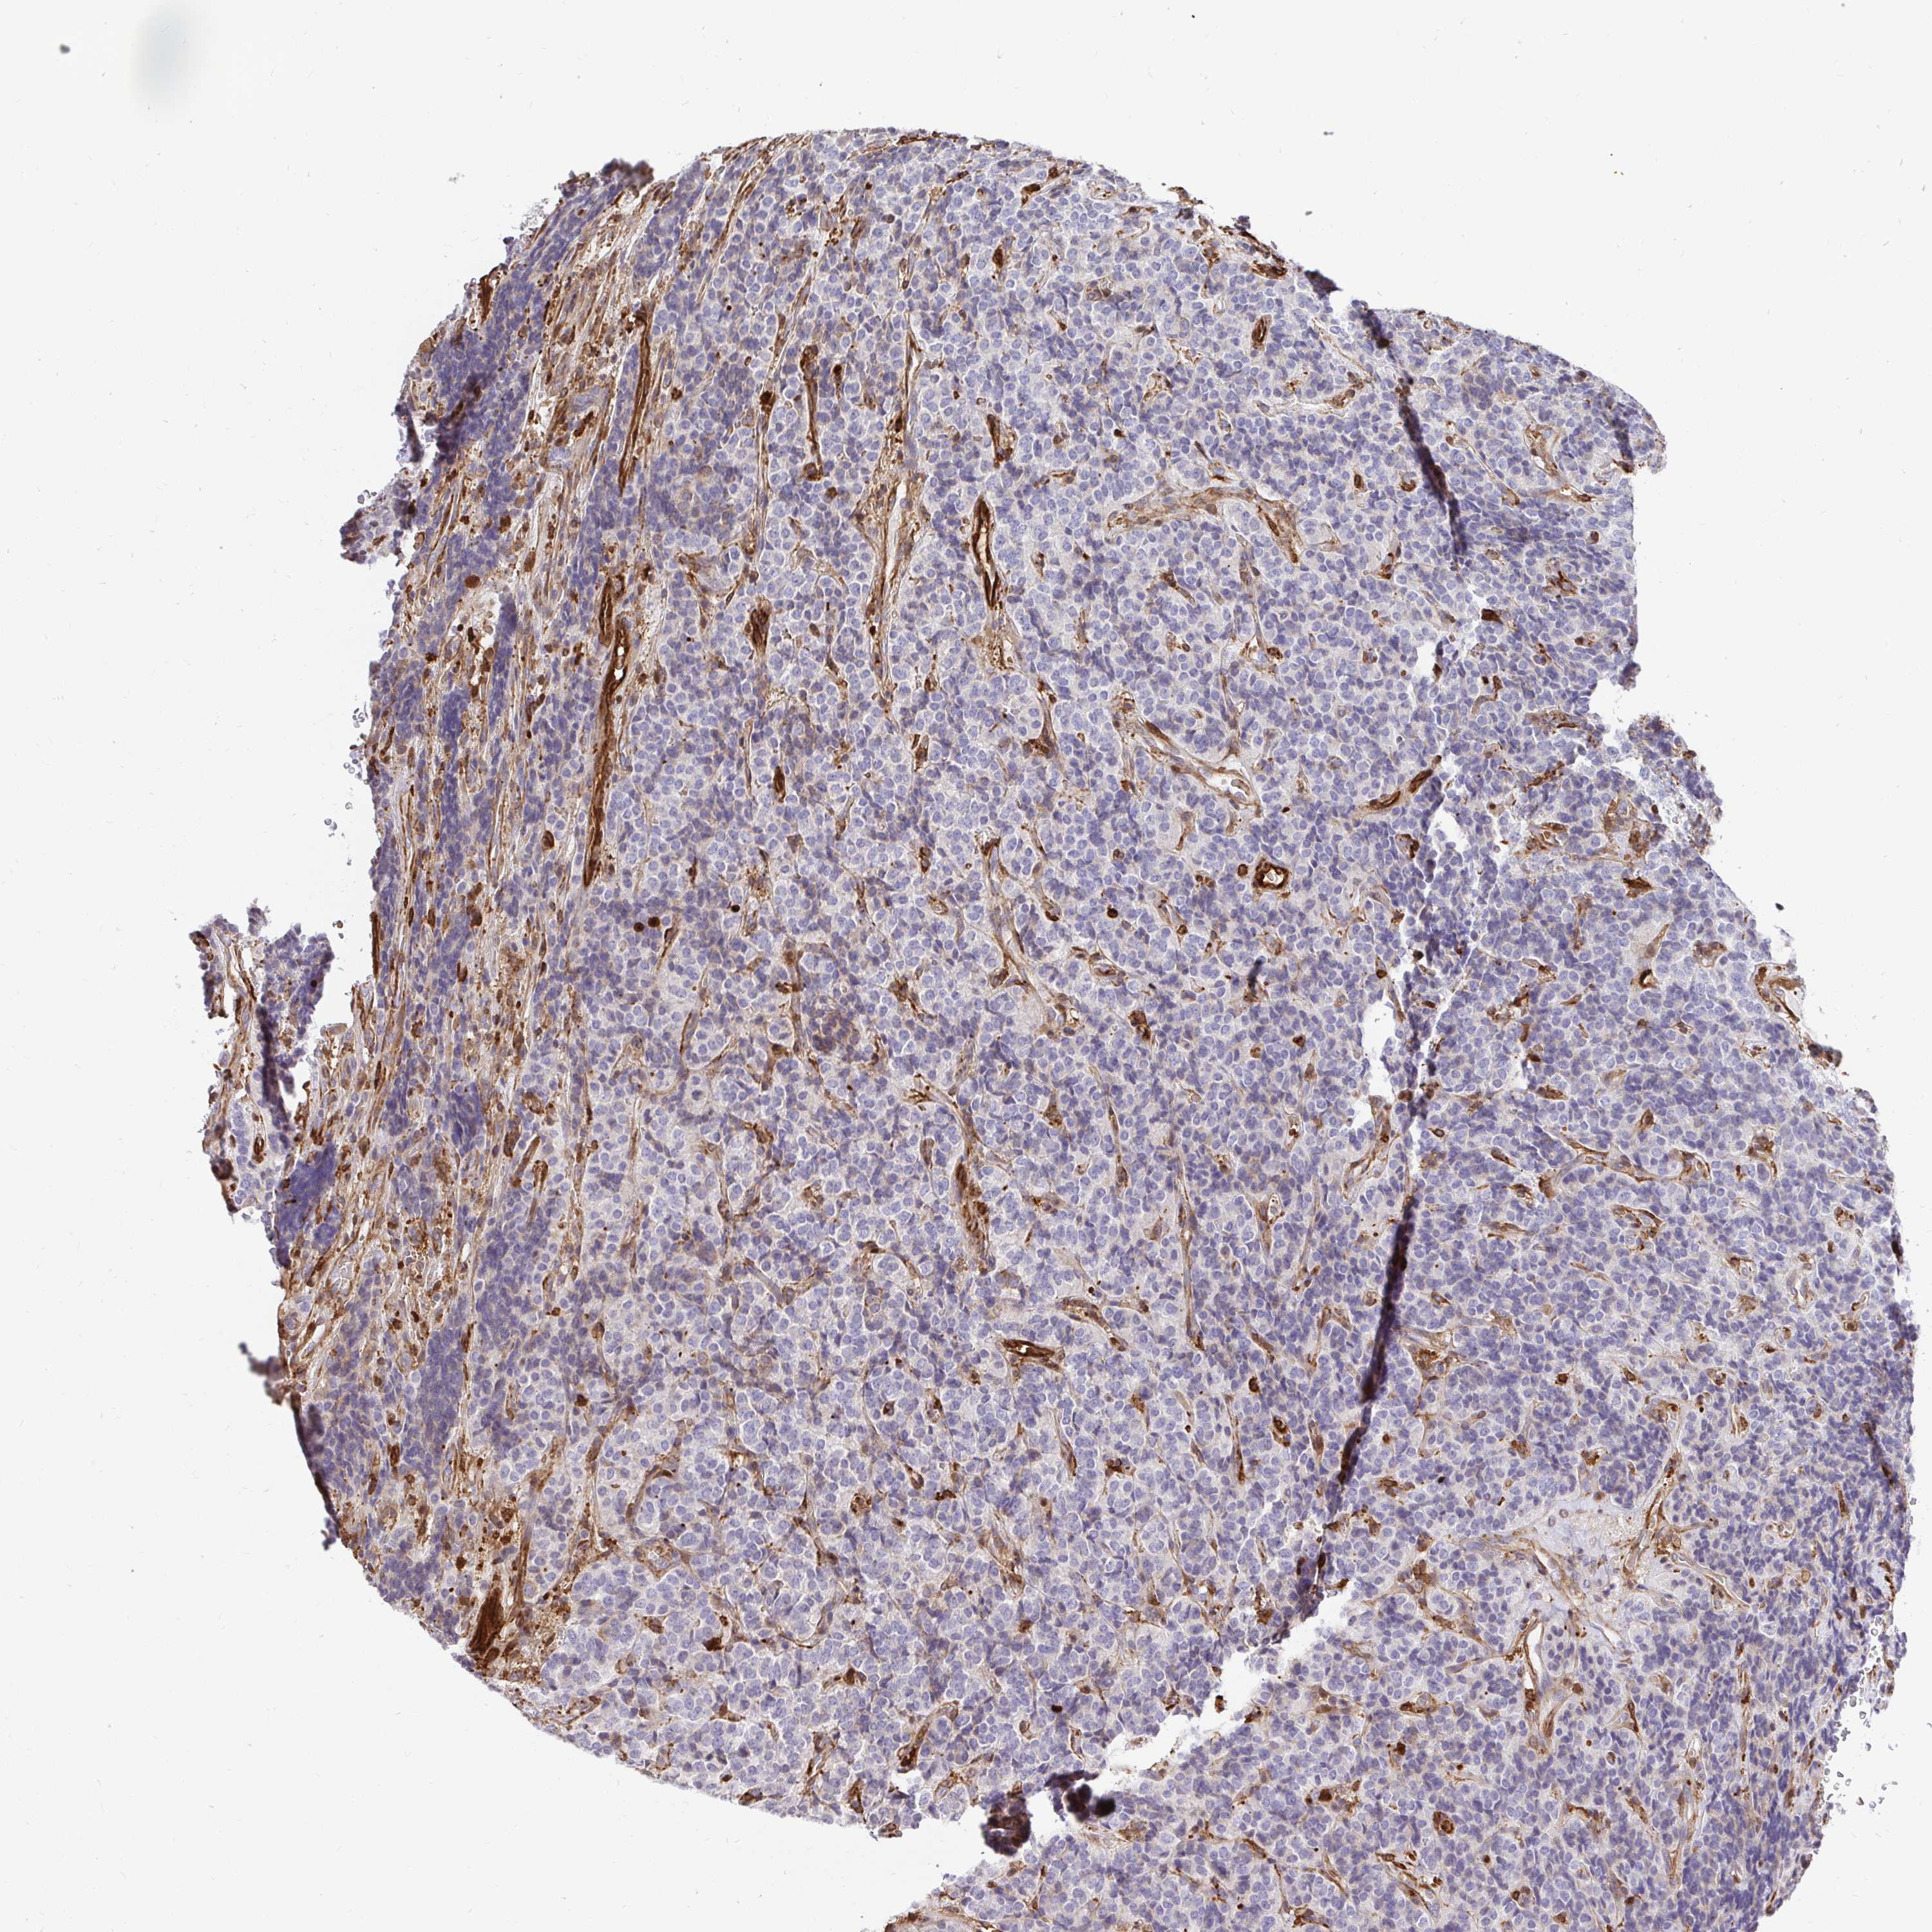

CARCINOID - Protein expressioni

A mouse-over function shows sample information and annotation data. Click on an image to view it in a full screen mode. Samples can be filtered based on level of antibody staining by selecting one or several of the following categories: high, medium, low and not detected. The assay and annotation is described here.

Each image is clickable and will lead to virtual microscopy that enables deeper exploration of all samples and also displays staining intensity scores, fraction scores and subcellular localization as well as patient and tissue information for each sample.

Antibody CAB010823

Staining

High

Medium

Low

Not detected

Carcinoid, malignant, NOS